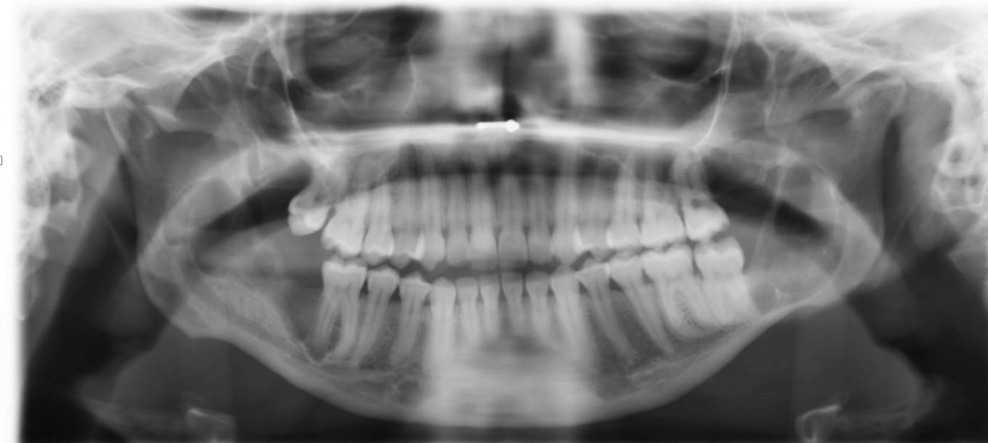

Cette femme de 26 ans consultait pour des douleurs récidivantes au niveau des dents de sagesse. Elle avait comme antécédents un asthme et une néphrectomie du rein droit en raison d’une dysplasie. Sa consommation tabagique était estimée à 6 paquets-année. Le panoramique dentaire (fig. 1 ) montrait quatre images radioclaires entourant les dents de sagesse. La patiente était alors adressée dans le service de chirurgie où un Cone Beam (fig. 2 et 3 ) permettait d’évaluer la taille des lésions kystiques ainsi que leurs rapports avec les structures anatomiques voisines. L’avulsion des dents de sagesse et l’énucléation des kystes étaient réalisées. L’examen anatomopathologique des lésions notait une paroi kystique bordée par un épithélium malpighien ortho- ou parakératosique avec une hyperplasie des couches basales compatible avec des kératokystes bénins odontogènes.